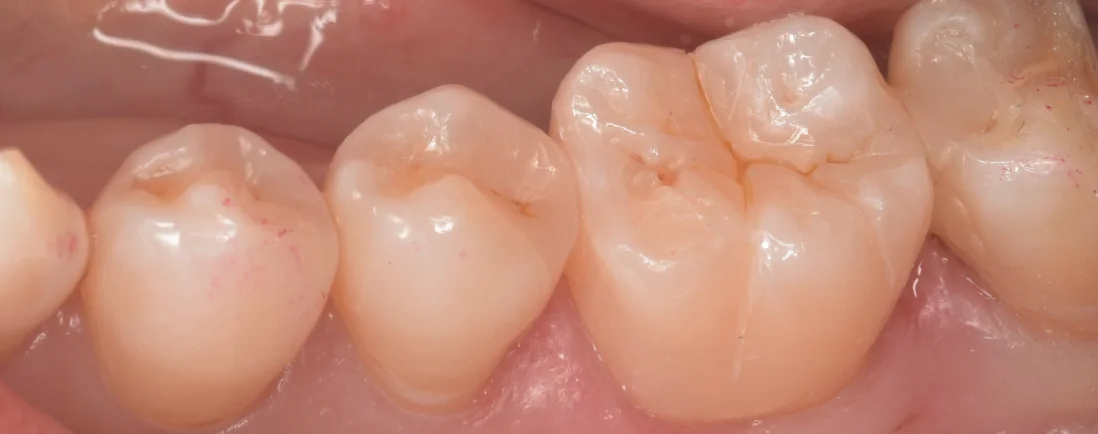

そして、詰め終わったのがこちらになります。

割と違和感なく自然に詰めることが出来たと思います。

予定よりも噛み合わせの調整が多くなってしまったため、細かい形態が消し飛んでしまったのが残念な部分ではありますけどね。。。

では、術前術後の比較です。

適合はしっかりと合わせておきましたので、食生活や力のコントロールに気をつけてなるべく長く使ってもらえると嬉しいです(●´ω`●)